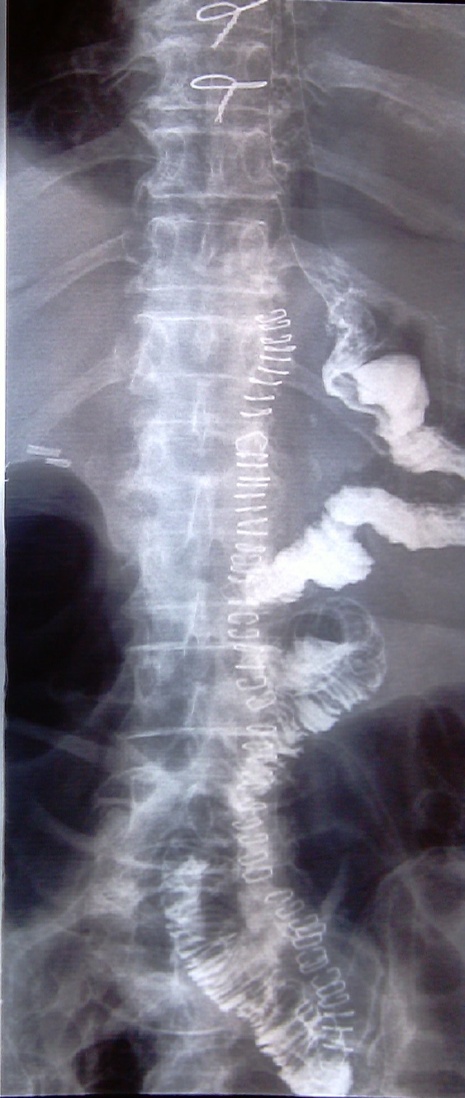

Έλεγχος στεγανότητας και βατότητας της οισοφαγονηστιδικής αναστόμωσης (Ευγενική παραχώρηση Dr. V. Penopoulos)